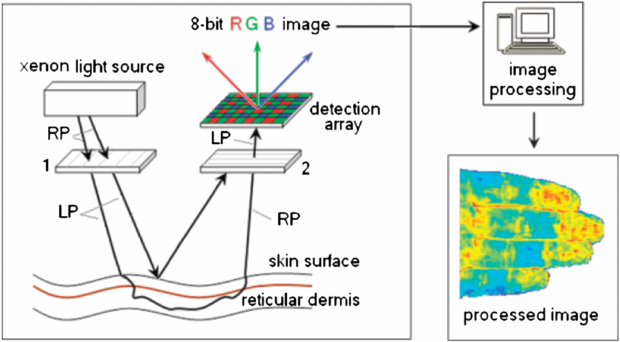

Photoacoustic (or optoacoustic) tomography (PT) is an umbrella term for a range of imaging methods that can provide detailed images of tissue types and blood oxygenation levels. PT can image blood vessels in highly scattering tissue and can discriminate between arteries and veins (Kruger et al 1995). An excellent review of the technology is given by Beard (2011).

PT combines optical absorption contrast and highly scalable spatial resolution i.e. from micrometer optical resolution to millimetre acoustic resolution. PT has three main embodiments: microscopy, computed tomography, and endoscopy (Hu and Wang 2010a, 2010b) with representative applications in microvascular-related physiological and pathophysiological research, including haemodynamic monitoring, chronic imaging, tumour–vascular interaction (Ehling et al 2013), neurovascular coupling (Hu and Wang 2010a), and drug discovery biomarkers (Bednar and Ntziachristos 2012).